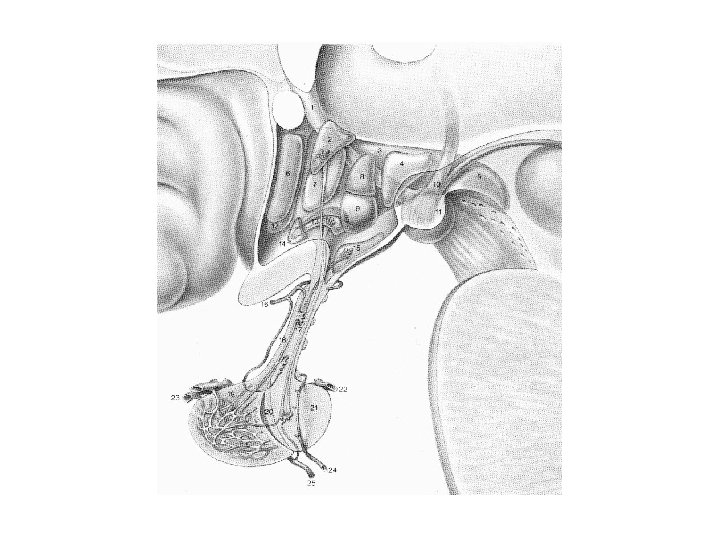

Hypothalamo-hypophysis rendszer Két részből, a nagysejtes hypothalamo-neurohypophysealis és a kissejtes tubero-infundibuláris rendszerből tevődik össze. A nagysejtes supraopticus és paraventriculáris neuronok vasopressint és oxytocint termelnek, axonjaik jelentős része (a supraopticus esetében az összes) a neurohypophysisben végződnek, ami quasi raktára a vasopressinnek és az oxytocinnak. A tubero -infundibuláris neuronok a hypophysis elülső részében levő endokrin sejtek neurohormonjaik termelésének szabályozását és felszabadításukat (release -t) végzik. A hypothalamus különböző részeiben termelődő neurohormonok nem közvetlen úton, hanem neurohumorális transzport révén jutnak a hypophysisbe: axonjaik az eminentia mediana vér-agy gát-mentes kapillárisaiba ürítik szállított termékeiket, melyek a portális erek révén jutnak a hypophysis elülső lebenyébe.

Hypothalamus szerepe a só- és vízháztartás szabályozásában A vasopressin a magnocellularis paraventricularis és supraopticus magokban termelődik. A vasopressint korábban antidiureticus hormonként (ADH) írták le, és ez az elnevezés ma is használatos a klinikumban. A vasopressin szintézisében és a neurohypophysisbe juttatásában, illetve az onnan történő felszabadításában két másik hormon az angiotensin II, és atrialis natriureticus hormon visz szerepet. Az előző a vesében termelődő renin-angiotensin rendszer aktív tagja, mely a vér-agy-gát-mentes subfornicalis szerven keresztül jut be az agyba, míg az utóbbit a preopticus area neuronjai termelik.

Nucleus paraventricularis hypothalami A hypothalamus egyik legjelentősebb magja, magno- és parvocellularis részre osztható. A magnocelluláris neuroszekretoros sejtek vasopressint és oxytocint termelnek, axonjaik a tractus hypothalamo-hypophysealis egy részét alkotják, és a hypothalamus hátulsó lebenyében végződnek. A parvocelluláris neuroszekretoros idegsejtek több peptiderg neurohormont (corticotropin-releasing hormon – CRH, thyrotropin-releasing hormon – TRH, vasopressin) és neuromodulátort (neuropeptidet) termelnek. A parvocellularis neuronok egy része az eminentia mediana portális erei révén juttatja el termékét a hypophysis elülső lebenyébe, másik részük a nyúltvelőbe és a gerincvelőbe projíciál. A CRH-termelő idegsejtek révén a paraventriculáris magot a stresszválasz központi részének, a „hypothalamohypophysis-mellékvesekéreg szabályozó rendszer” („HPA axis”) kiinduló pontjának tekintik.

Vasopressin